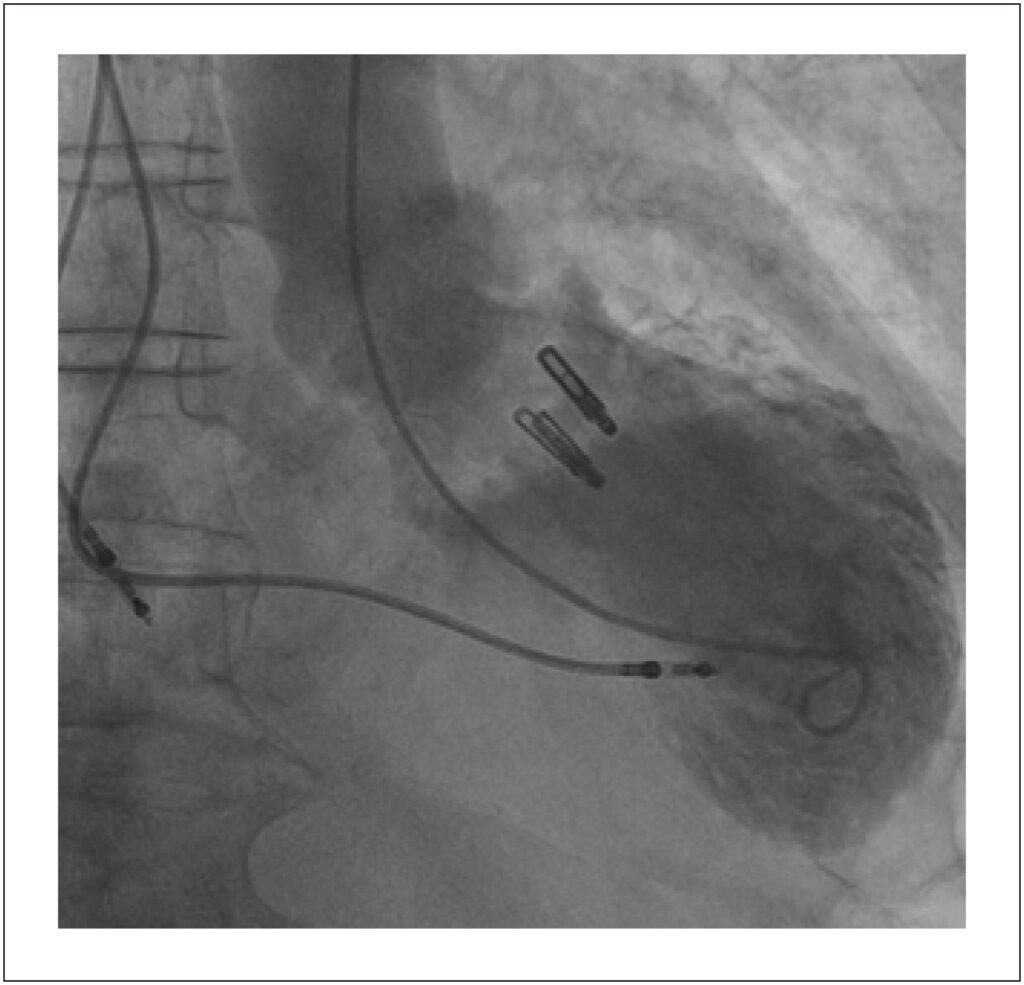

Takotsubo Syndrome After Percutaneous Mitral Valve Repair With Mitraclip®: A Case Report